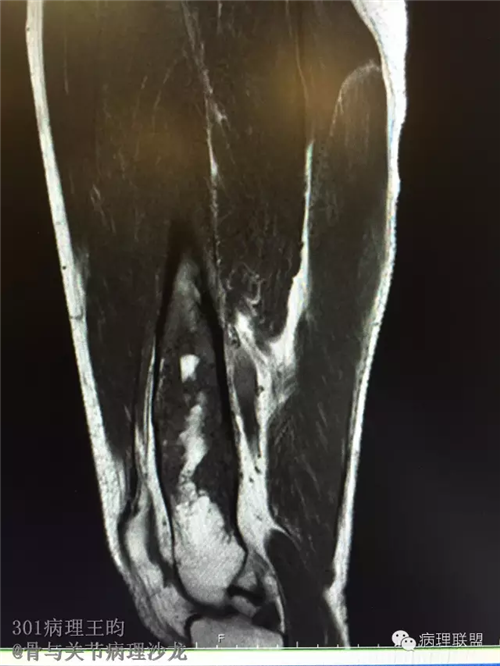

右股骨髓内高分化低级别骨肉瘤or骨纤维异常增殖症(Fibrous Dysplasia)?

男,36岁,活动后疼痛,发现右股骨远端肿瘤。